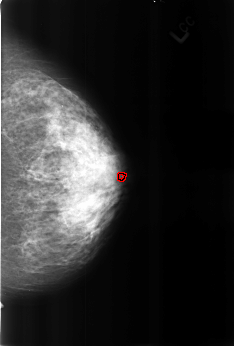

B_3168_1.RIGHT_CC

RIGHT_CC LINES 4552 PIXELS_PER_LINE 3064 BITS_PER_PIXEL 12 RESOLUTION 50 OVERLAY

FILE: B_3168_1.RIGHT_CC.OVERLAY

TOTAL_ABNORMALITIES 2

ABNORMALITY 1

LESION_TYPE CALCIFICATION TYPE COARSE DISTRIBUTION N/A

ASSESSMENT 2

SUBTLETY 5

PATHOLOGY BENIGN_WITHOUT_CALLBACK

TOTAL_OUTLINES 1

BOUNDARY

ABNORMALITY 2